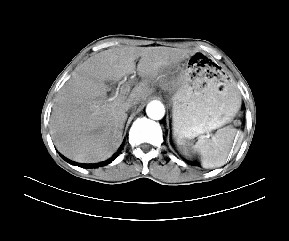

标题: CT19533:病变来源于哪?

患者,男,发现上腹部包块两月余。

病变位于肝胃间隙,实际就是位于小网膜囊(左肝下后间隙),呈轻度不均匀性强化,腹腔内及腹膜后见多发肿大淋巴结。所以我考虑肝胃间隙恶性胃肠间质瘤并淋巴结转移。

病灶强化不显著,灶周及腹膜后见多量淋巴结肿大,考虑淋巴瘤可能,其次考虑间质瘤

病灶与胰腺分界不清,来源于胰腺?

强化后病变与胃壁分界清楚,并且血供不是来源胃壁血管。考虑胰腺颈体癌并腹腔腹膜后淋巴结转移。